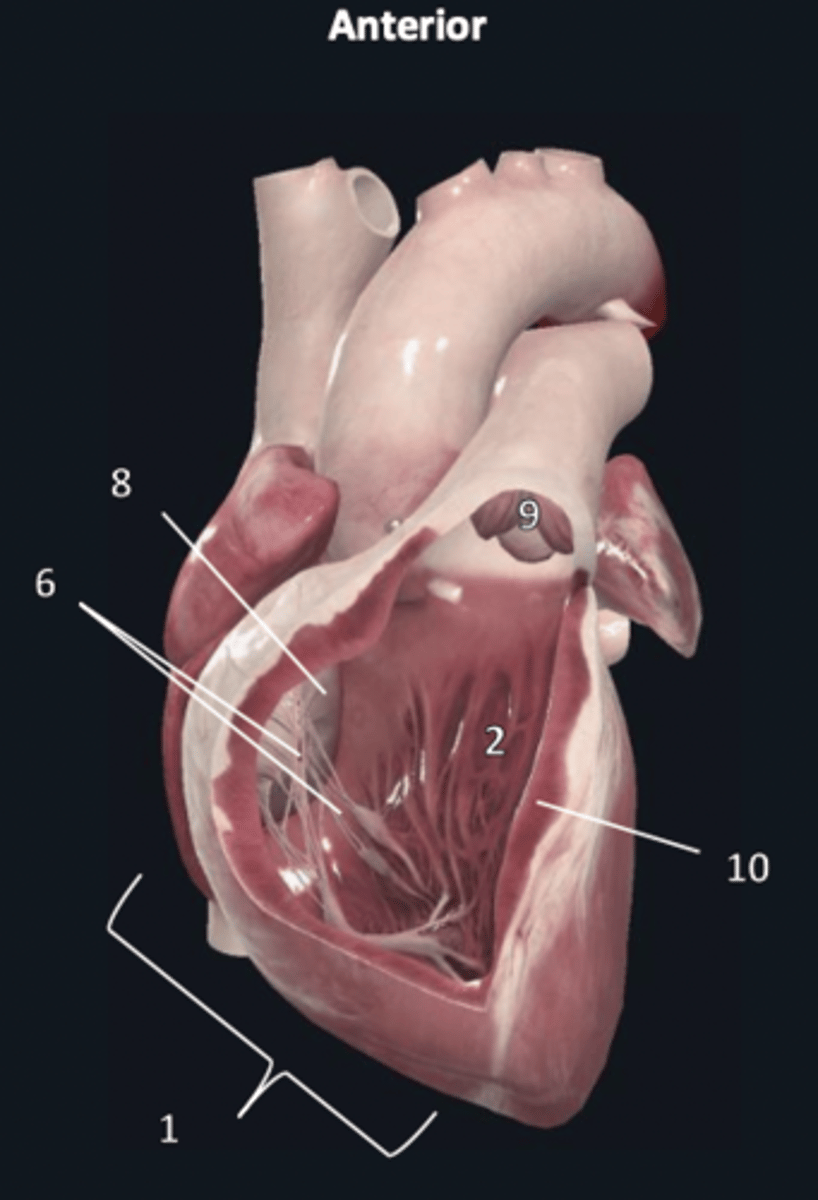

right ventricle

1

trabeculae carneae

2

septal papillary muscle

3

anterior papillary muscle

4

inferior papillary muscle

5

chordae tendineae

6

moderator band

7

tricuspid valve

8

pulmonary semilunar valve

9

interventricular septum

10